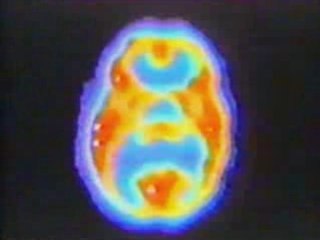

Evaluación del Desarrollo infantil